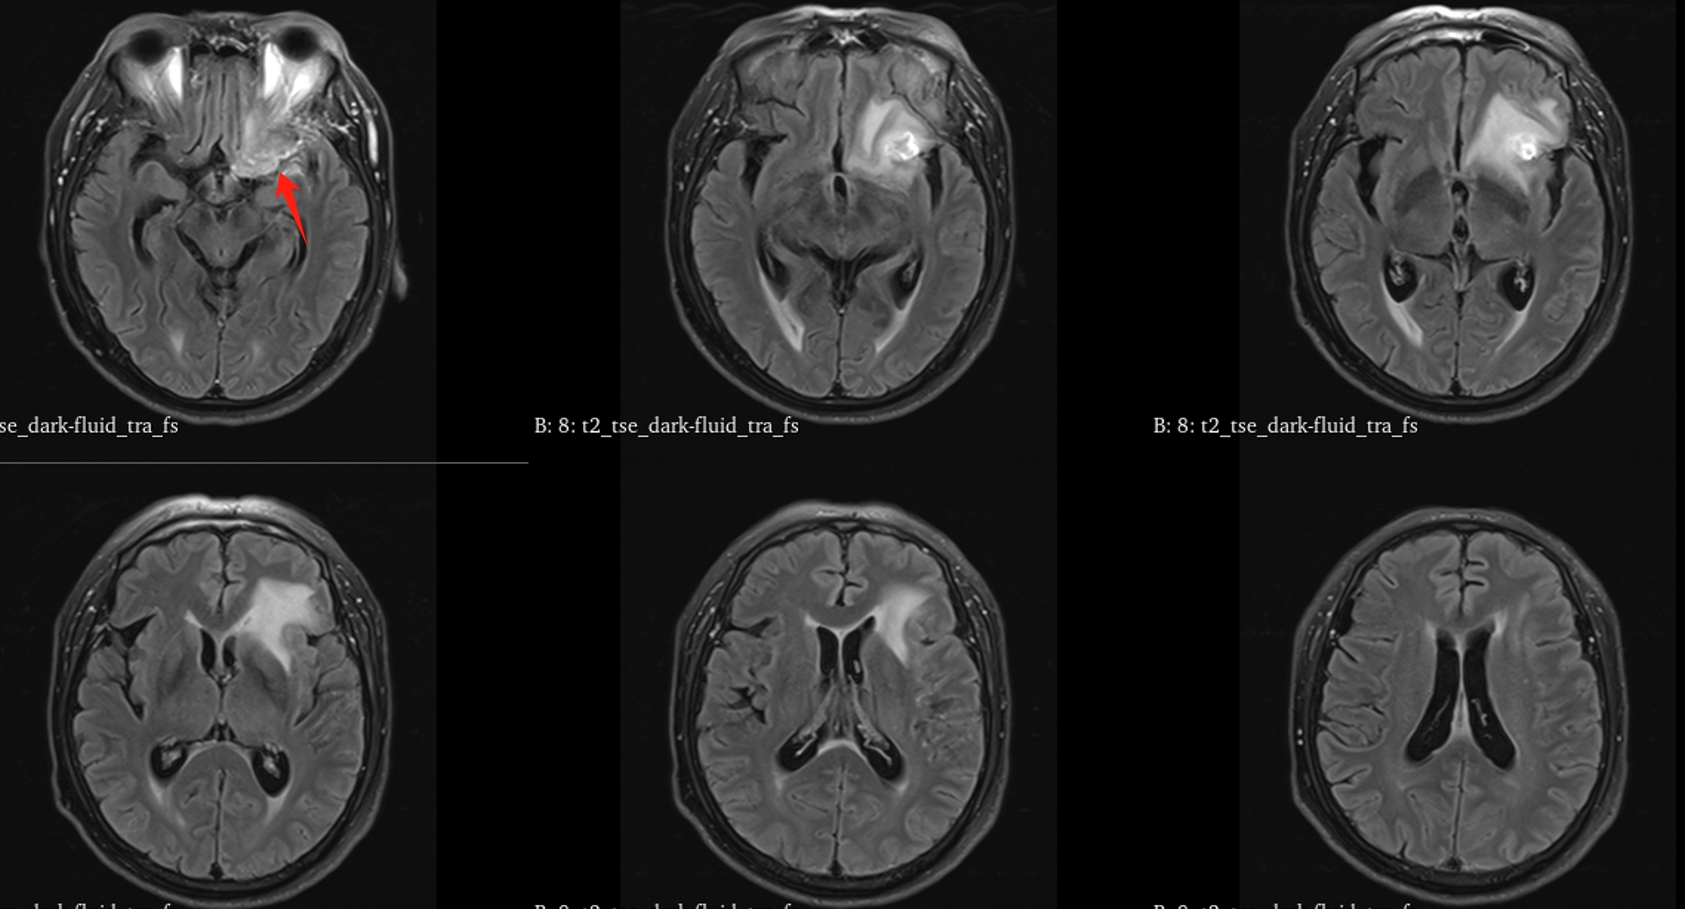

该患者入院后完善常规颅脑影像学检查,左侧颞叶病变,疾病性质不详,转移瘤、胶质瘤、炎症类疾病均不能排除,遂行PET-CT检查,提示左侧颞叶高代谢,淋巴瘤不能排除。组织MDT会诊建议可先行腰椎穿刺查脑脊液脱落细胞学、感染指标,若仍不能确诊,可进一步行开颅病灶切除,术中快速冰冻,根据冰冻结果决定手术手术策略。患者脑脊液脱落细胞学结果:较多淋巴细胞,少许单核细胞及个别中性粒细胞,未见异形细胞,脑脊液常规、生化、脑脊液培养未见细菌生长,诊断仍不能明确,且患者病情进展迅速,患者神志呈昏睡状态,颅脑MRI提示病变较前明显增大(影像学检查间隔两周),且水肿明显加重,遂行开颅病变切除术。术中见部分病变累及蝶骨嵴硬膜,病变质地硬韧,内有多个囊腔,囊内容物为黄色粘稠样脓性物质,留取囊液及实性部分送快速冰冻,在等待冰冻过程中,进一步探查见肿瘤侵犯左侧颞叶,该部位肿瘤质地相对软,无包膜,与周围脑组织无边界,血运不丰富,内有多个囊腔,且肿瘤侵犯侧裂池、颈动脉池,左侧视神经、颈内动脉、大脑中动脉均被病变包绕,且该处肿瘤质地偏硬韧。术中快速冰冻提示组织大片变性坏死,伴胶质增生及淋巴增生。结合病变质地及冰冻结果,考虑为非肿瘤性疾病,可能为炎性病变伴肉芽肿形成可能性大,且肿瘤质地硬韧,累及范围广泛,难以全切,遂行肿瘤大部分切除后结束手术。术后病理结果明确后予以伏立康唑、醋酸卡泊芬净抗真菌治疗。在治疗过程中患者先后出现脑出血、脑梗塞,最终因治疗周期长,花费高、效果不确定等因素,家属放弃治疗,于术后1月去世。

GM实验,GM是曲霉菌细胞壁的主要成分,是疾病早期释放至体液中的抗原之一。据报道,脑脊液GM试验诊断ICA的敏感度及特异度分别为88.2%及96.3%,且阳性预测值及阴性预测值均超过90%,脑脊液GM水平与曲霉菌感染严重程度相关,监测该指标可评价治疗效果及预后。影像学检查具有多样性,多为反复慢性炎症、肉芽肿样改变,部分易累及颅底。

目前确诊ICA仍依赖于病灶切除或活检,获得组织病理学、直接镜检或培养证据。《颅内曲霉菌病诊治中国专家共识》推荐:当临床症状怀疑ICA时,应尽早行脑脊液检查(常规、生化、培养、G试验、GM试验及mNGS)及颅脑MRI平扫+增强检查。怀疑窦源性ICA时,还应加做颅底CT检查。当临床症状符合ICA,但上述检查结果为阴性时,可重复送检。条件允许时,及时行标本镜检与培养获得确切证据。尤其是对于长期应用激素、免疫功能缺陷高危患者。